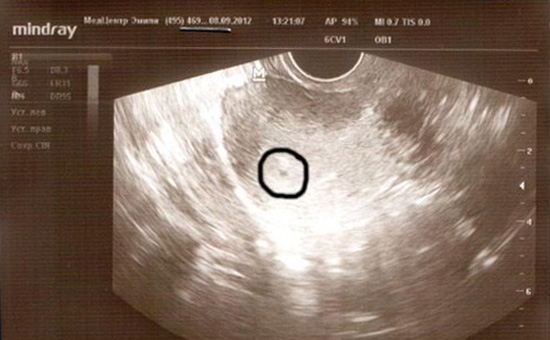

Nhờ sự tiến bộ của công nghệ y học, mẹ bầu có thể thực hiện siêu âm khi thai nhi mới chỉ đang ở tuần 4. Mặc dù không thể nhìn rõ em bé nhưng hình ảnh siêu âm thai 4 tuần tuổi sẽ phần nào thỏa mãn được sự tò mò, háo hức của người làm cha làm mẹ. Kết quả siêu âm thai 4 tuần sẽ có các thông tin như kích thước túi thai hay vị trí thai làm tổ. Tuy vậy, vẫn chưa có gì chắc chắn để khẳng định thai 4 tuần đã vào tử cung chưa.

Để mô tả chính xác nhất, phôi thai lúc này chỉ như một chú nòng nọc siêu nhỏ với phần đầu lớn, phần thân nhỏ cùng các chồi xung quanh (tay, chân sau này). Các chỉ số khác chỉ chính xác ở mức tương đối khi dựa vào hình ảnh thai nhi 4 tuần tuổi. Bác sĩ sẽ hẹn mẹ lịch khám lại ở những tuần tiếp theo để thấy thai nhi rõ nét và có nhiều thông tin hơn.

Kết quả siêu âm thai 4 tuần sẽ có các thông tin như kích thước túi thai hay vị trí thai làm tổ. Tuy vậy, vẫn chưa có gì chắc chắn để khẳng định thai 4 tuần đã vào tử cung chưa. Mỗi mẹ có một thể trạng khác nhau nên thời gian thụ thai, làm tổ sẽ nhanh hay chậm không giống nhau.